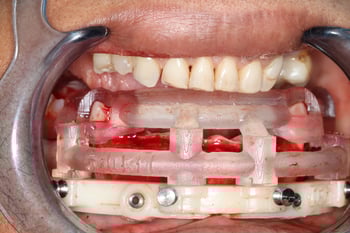

With the proposed tooth position defined, we predicted the ideal lower occlusal plane, which revealed the need for significant bone reduction.

Our primary objective was to achieve proper vertical dimension and sufficient restorative space to support a future implant overdenture, with a minimum clearance of 12–15 mm.

Computer-generated surgical guides were then used to facilitate precise bone reduction in both arches, reinforcing the value of prosthetic-driven planning.